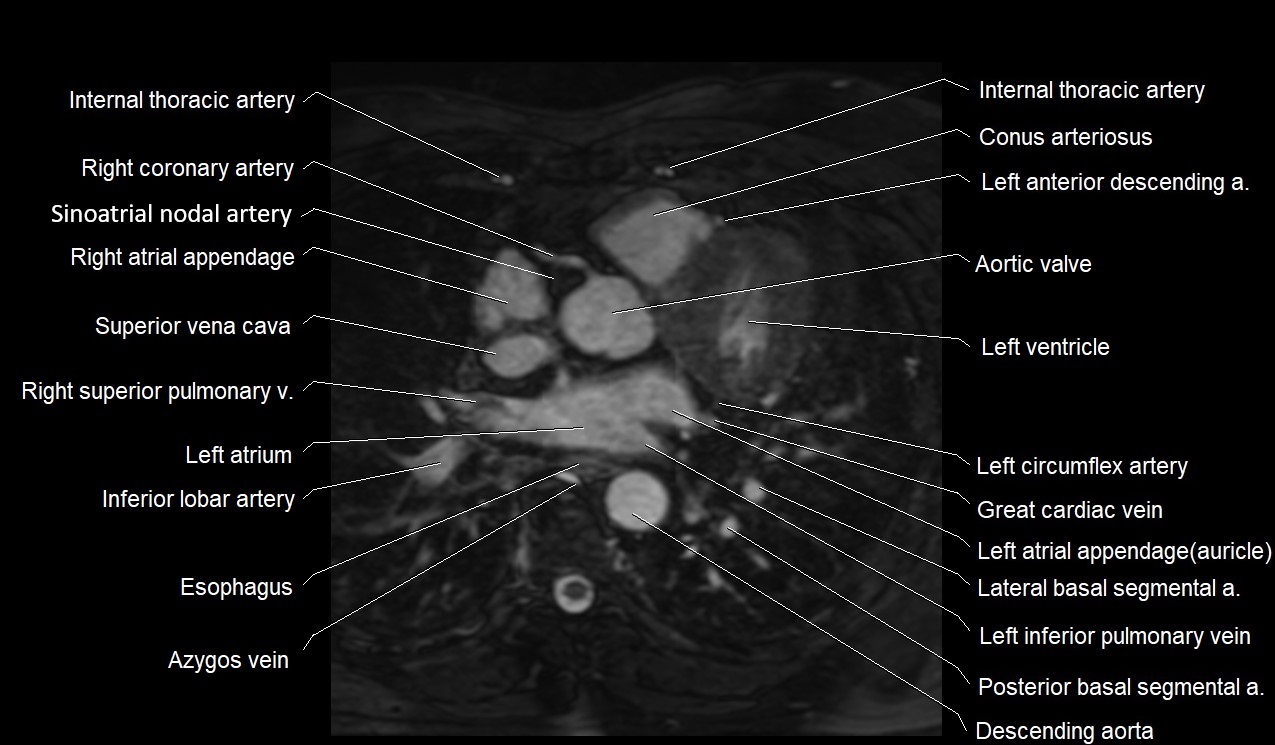

MRI image